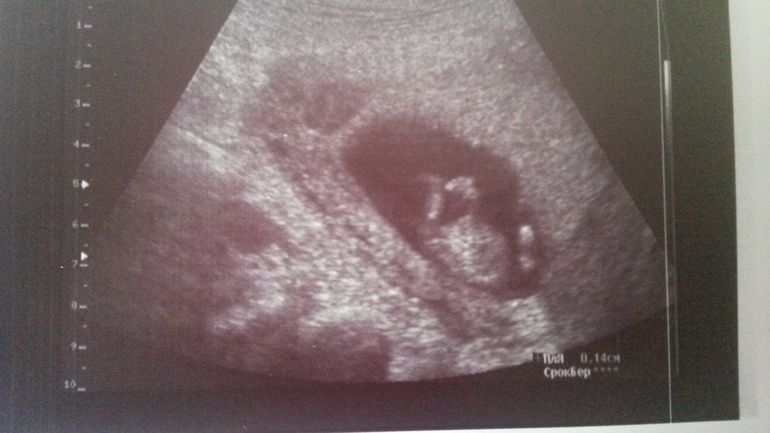

Поводила врач значит аппаратом...смотрим пол...

Она мне: - Про пол не буду ничего пока говорить... (знает, что мы девочку хотим)

Я - Да я уж сама вижу...Похоже на мальчика :) (сама в шоке, настолько я была уверена, что жду девочку)

Посмотрели в разных ракурсах...Все же мальчик выходит, как ни крути...))) этот писюн, понимаешь ли...

Будем ждать 18 недель, 2-го скрининга... За это время киндер подрастет, будет побольше, за одно посмотрим еще раз пол. Ну, вдруг писююн отвалится, т-т-т.

Под катом пара фоточек нашего чуда) На второй это нижняя часть пузика и ножки)